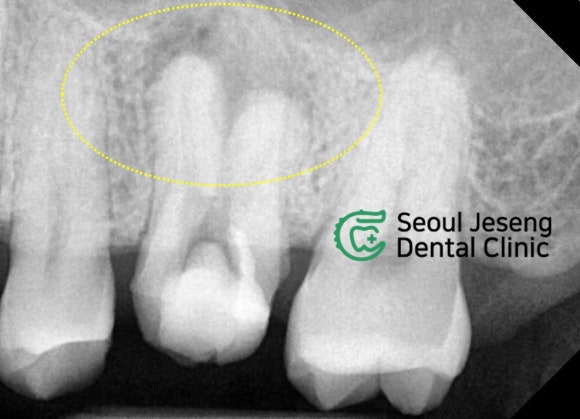

사진 속 노란 동그라미를 주목해주세요.

한창 신경치료 중인 어금니가 하나 보입니다.

치아 독사진을 찍어봅니다.

치아 뿌리 끝을 둘러싼 까만 그림자가 보입니다.

까만 그림자 = 염증 입니다.